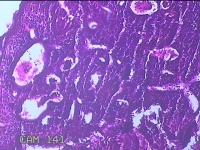

性别年龄35岁临床诊断人乳头瘤病毒感染,宫颈上皮内肿瘤,贫血

一般病史HPV12种亚型(+),TCT低级别病变。阴道镜见醋白薄层,碘着色。

标本名称宫颈3点、7点、9点、12点组织

大体所见1.“宫颈3点组织”:灰白粉红色组织0.7x0.5x0.2cm两块。 2.“宫颈7点组织”:灰白粉红色组织0.7x0.5x0.2cm一块。 3.“宫颈9点组织”:灰白粉红色组织0.5x0.3x0.2cm一块。 4.“宫颈12点组织”:灰白粉红色组织0.8x0.7x0.2cm两块。